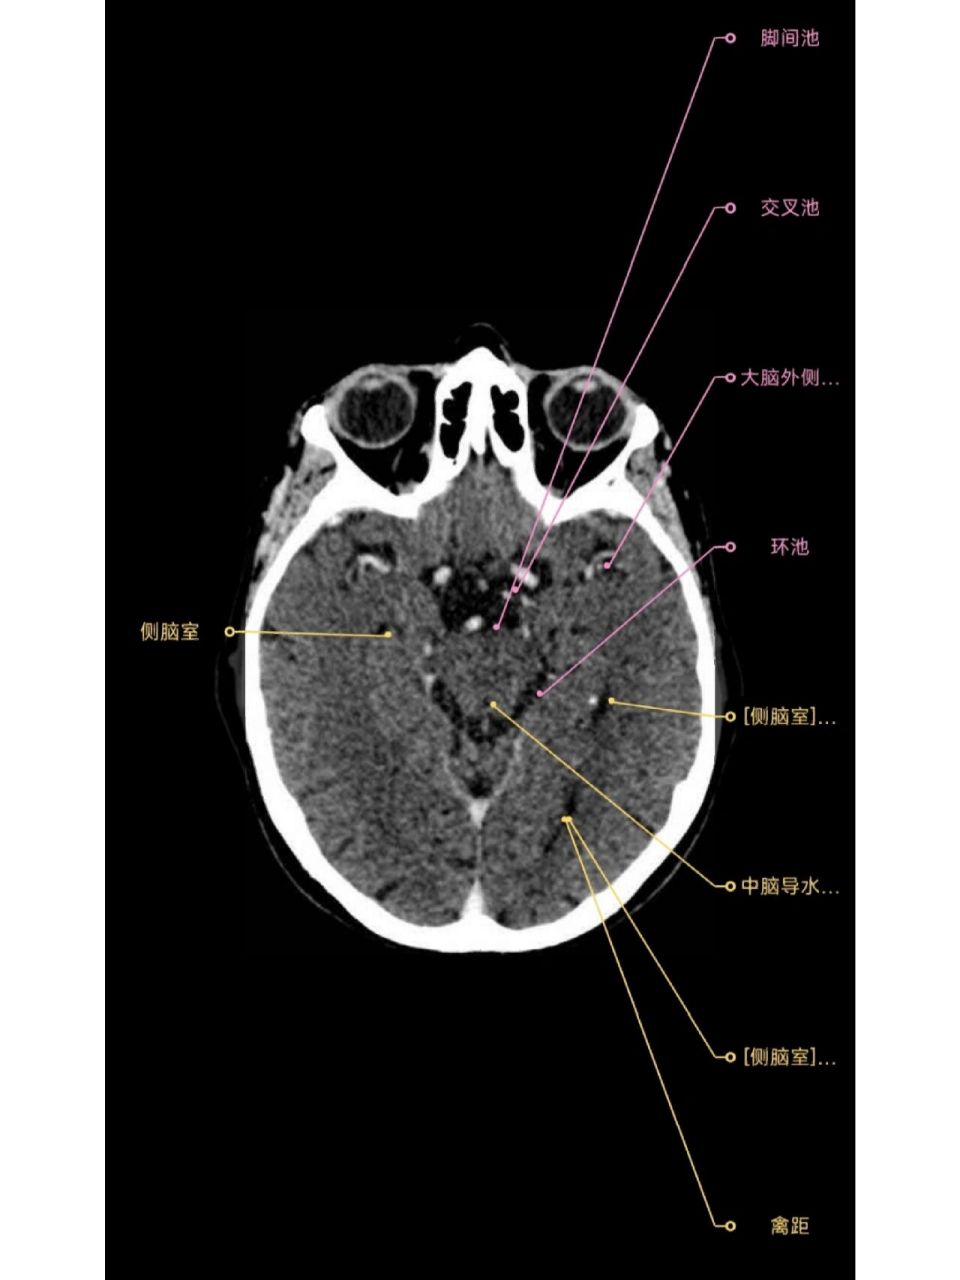

脑池 环池,脚间池,交叉池,外侧窝池